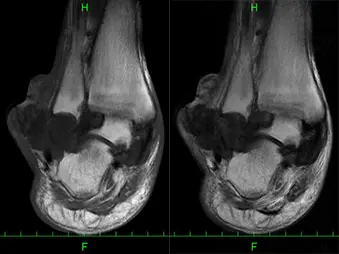

MRI:T1強調画像で低信号から中等度の信号を示し、T2強調画像で内部不均一な低信号から中等度の信号を示す腫瘤を認める。(図2)

左:T1強調画像 右:T2強調画像

単純X線ではover hanging margin徴候が特徴的で、関節内の尿酸塩結晶による炎症を繰り返し、骨内へ侵蝕することで骨膜が刺激され骨が痛風結節を取り囲むように突き出ることにより生じるとされている。また、変形性関節症とは異なり骨軟部病変があるにも関わらず、関節裂隙が保たれている場合が多く、更に骨内侵蝕もしくは骨内痛風結節では境界明瞭な長円形または円形の打ち抜き像も特徴である。MRI所見は、YuらはT2強調画像で低から中等度信号の骨破壊像を示す腫瘤を認めれば痛風結節が疑われるとし、またChenらは関節内にT2強調画像で低信号領域があり、ガドリニウム(Gd-DTPA)で周囲が不均一に増強される場合は痛風結節が示唆されると報告している。ただし、画像所見だけでは診断に至ることは困難なことが多く、最終的には病理診断により確定診断に至ることが多い。